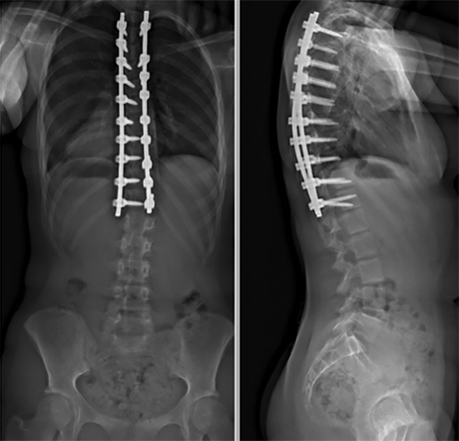

B) Fusion